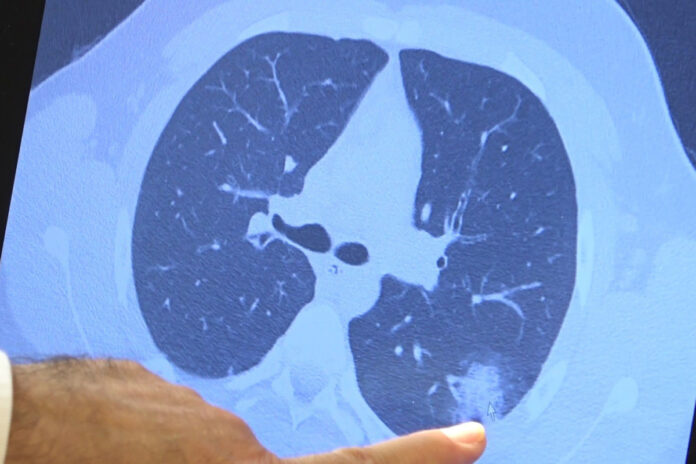

Aşı olmayan ve korona virüse yakalanan 14 yaşındaki çocukta ciddi akciğer tutulumları görüldü

Korona virüste aşılama yaşı her geçen gün düşerken aşı olmayan çocuklarda da ciddi akciğer tutulumları görülmeye başladı. 12 yaş üzeri kronik rahatsızlığı olan hastalara artık aşılama yapılabiliyor. Göğüs Hastalıkları Uzm. Prof. Dr. Şevket Özkaya ise aşı olmamış kronik rahatsızlığı olan 14 yaşındaki bir çocuğun akciğerlerinde oluşan ciddi tahribatı gözler önüne serdi.

Bazı vatandaşlar hala aşı olmakta tereddüt etmeye devam ederken korona virüs çocuk grubundaki hastaları da etkilemeye başladı. VM Medical Park Samsun Hastanesi Göğüs Hastalıkları Kliniği’nden Prof. Dr. Şevket Özkaya ise aşı olabilecek yaş grubundaki çocukların bir an önce aşılanması gerektiğine vurgu yaptı. 14 yaşında, kronik rahatsızlığı olan ve akciğerlerinde tahribattan dolayı ciddi öksürük, ateş ve nefes darlığı çeken bir hastanın akciğerlerini inceleyen Prof. Dr. Özkaya, “14 yaşındaki kronik rahatsızlığı mevcut olan bir genç hastamızda ciddi akciğer tutulumları var. Her iki akciğerinde de yaygın buzlu cam ve konsolidasyon alanları var. Bu yaştaki çocuklarda beklemediğimiz bir durumdur. Okullarımızda da bu risk var. Okullarımızın açık kalmasının ve sağlık sistemimizin kitlenmemesi için mutlaka aşı olmalıyız. Çocuklarımıza rol model olmalıyız. Şu anda hastanelerimiz hastalara yetişebiliyor. Yatak sayımız yeterli. Ancak kontrollü sosyal hayatımızı düzene sokmadıkça ve aşı olmadıkça, gelecekte hastanelerde yatak sayısı sıkıntısı çekebiliriz” dedi.